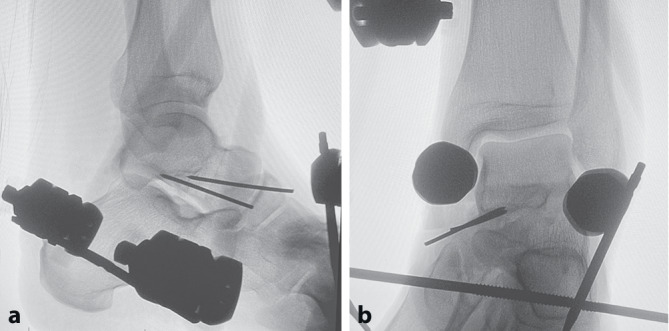

Background: Subtalar dislocations (simultaneous dislocations of the talocalcaneal and talonavicular joints) without concomitant fracture are rare and account for 1-2% of all dislocations. The treatment has been described in several case reports and consists primarily of closed reduction with the patient under anesthesia followed by immobilization.

Case: A 30-year-old male patient sustained a multidimensional nonfractured dislocation of the ankle joint with a predominantly subtalar component (luxatio subtalolateralis) while climbing. As it turned out later, a closed reduction was not possible due to interposition of the tendons of the posterior tibialis muscle and the flexor digitorum pedis longus muscle, so that an open reduction had to be performed. The full extent of the injury could only be assessed during the surgical exploration. The patient was treated in an external fixator for 12 weeks. Subsequently, physiotherapy was initiated. After only 6 months postoperatively the patient showed good mobility, functionality and resilience in the affected ankle joint. After 30 months the patient was free of symptoms. The prolonged immobilization after subtalar dislocation using an external fixator over a total period of 12 weeks, as performed in this case report, demonstrated good long-term functional outcomes.